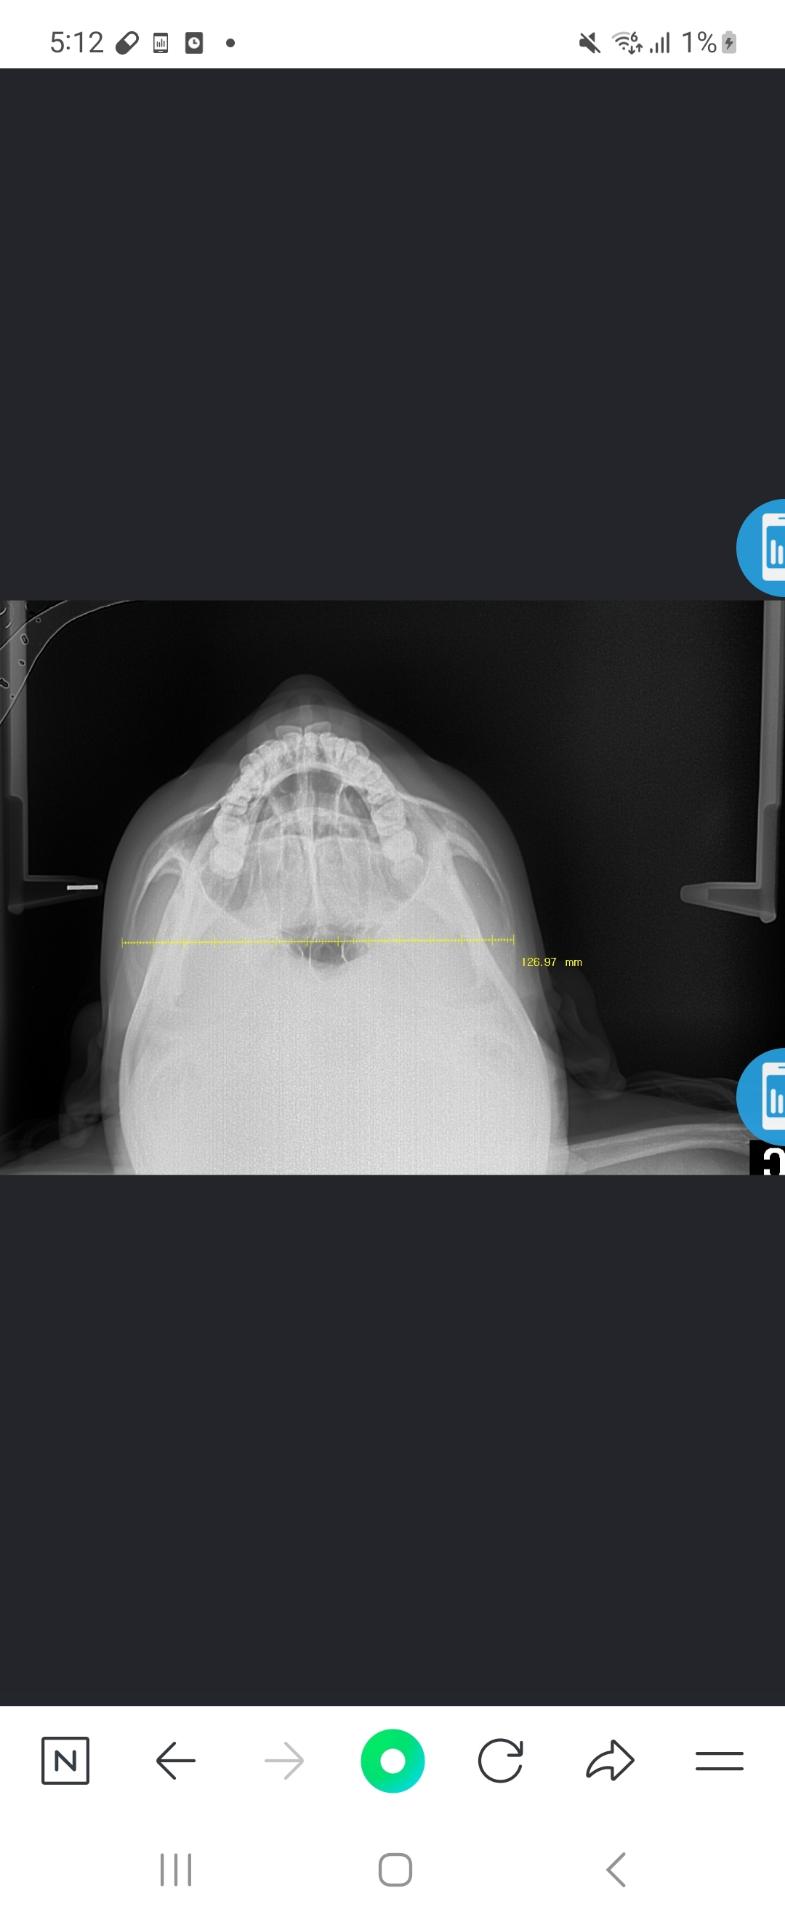

얼굴뼈가 커지는병 도와주세요 엑스레이사진

7월달에 제가 성형외과에서 잰 옆광대수치가 12.6cm였습니다 어제 정형외과병원에서 동일한자세로 턱들고 찍은수치가15.8cm로 4개월만에 옆광대거리가 성인21살인데도 3.2cm이상이 자랐는데 어떻해야할지모르겠습니다작년과 올해5월에 말단비대증피검사를 한번해서 정상이나왔습니다첫번째사진이 7월 두번째사진이 어제찍은사진인데 뼈가 많이 넓어졌는데 원인을모르겠어요..marpe악궁확장을 많이돌려서 넓어진걸까요

• 2번 째 사진